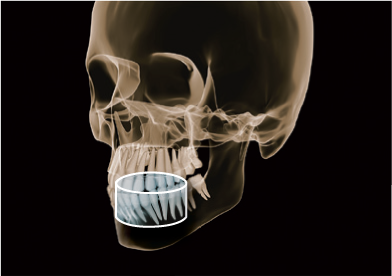

Z najnowszym aparatem Orthophos SL 3D, Twoja praktyka będzie przygotowana na każdy rodzaj leczenia. Przełomowa technologia sensora panoramy DCS oraz funkcja

Sharp Layer – zaspokoją potrzeby lekarzy, którzy wymagają maksimum szczegółów z obrazu panoramicznego. 3D daje Ci wybór pomiędzy objętością 11 cm x 10 cm, obrazująca pełne łuki szczęki i żuchwy wraz z sąsiadującymi strukturami, a 8 cm x 8 cm dająca wystarczającą ilość informacji diagnostycznych dla lekarzy ogólnych i implantologów.